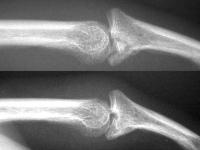

First impression was that the palmar fragment was probably big enough to take down and reinsert. However, comparison of films shortly after the fracture (above) and at two months (below) confirms the injury as a healed comminuted central impaction fracture with splay and hinging of the volar cortex.